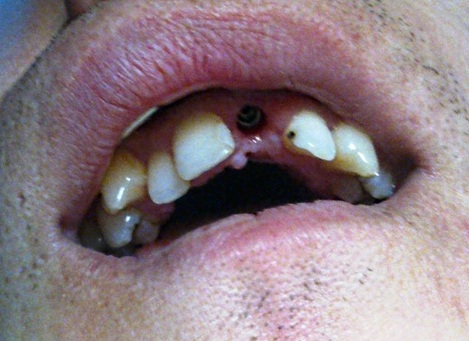

Patient K. (25 years old) turned to the clinic complaining about the aesthetic look of his 21st tooth.

Chronic periodontitis of the 21st tooth (Photo 1 and 2).

The examination found a sinus tract with an active inflammatory symptomatology. The endodontic treatment failed to give any positive results. There was made a decision to extirpate the 21st tooth along with simultaneous placement of Alpha Dent Implant with its diameter of 5 mm, 13 mm long and closure of soft tissue defects with PRP membrane. The surgery was carried out without immobilization of mucosa-periosteal graft making it possible to attain a good aesthetic look of the gingival edge and harmonious “rose-and-white” ratio.